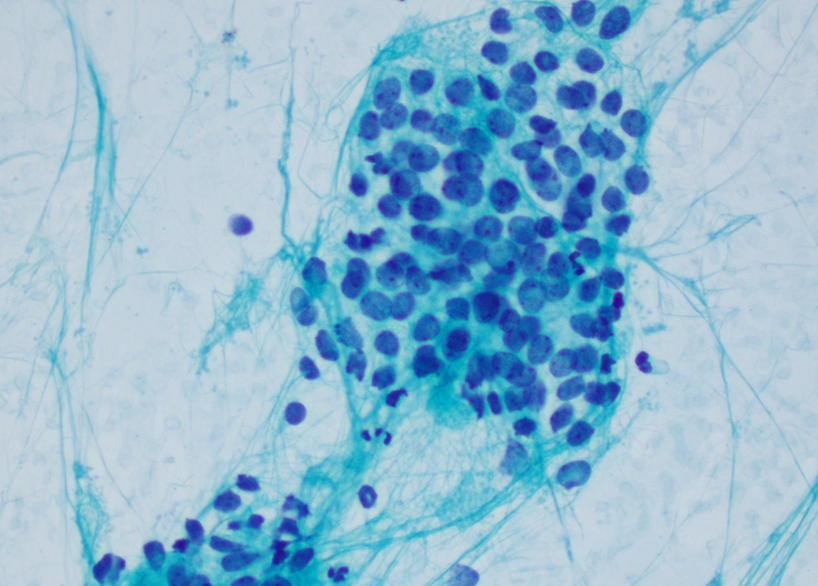

Cytology description

- Uniform small round cells (Diagn Cytopathol 2020;48:1098, Thorac Cancer 2016;7:602)

- Fine chromatin

- Occasional nucleoli

- Scant to indistinct cytoplasm

- Occasional rosette-like structures

Cytology images